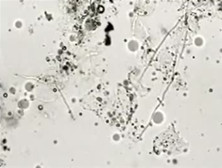

霉菌性阴道炎念即珠菌性阴道炎是一种常见的阴道炎,由白色念珠菌感染所致。临床表现主要为外阴瘙痒和白带呈白色稠厚豆渣样。本病发病率仅次于滴虫性阴道炎。最适于念珠菌繁殖的pH为5.5~6.5,当阴道中糖原增多,酸度增加时,即迅速繁殖引起炎症,故多见于孕妇、糖尿病患者及接受大量雌激素者,如长期应用抗生素,改变了阴道内微生物之间... [详情]